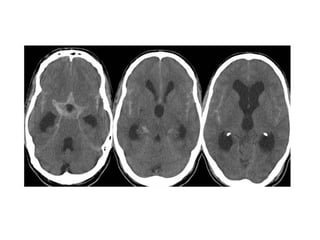

CT without contrast , cerebral venous thrombosis

CT without contrast , cerebral venous sinus thrombosis

*CT :

-Acute thrombus is hyperdense on precontrast CT

and expands the occluded sinus / vein (Dense

clot sign)

- Cord sign : is defined as a homogeneous ,

hyperattenuated appearance of thrombosed

venous sinuses , the hyperattenuated

appearance of the affected veins often being

named (the attenuated vein sign)